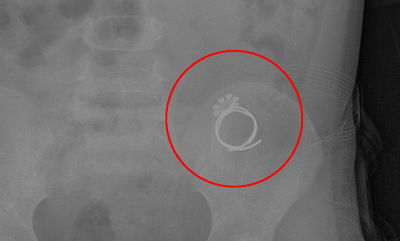

ילדה בת 3 הגיעה לבית החולים, לאחר שטבעת עמה שיחקה נתקעה לה בוושט. הרופאים שחששו מקצוותיה חדים, העבירו את הילדה לחדר הניתוח, והצליחו להוציא את הטבעת (בארץ)

זהו סיפורה של רות, ילדה בת שנתיים וחצי, שבלעה טבעת ונחנקה - עד שניצלה בדרך נס • ערב ראש חודש כסלו, 'כיכר השבת' מחפש את סיפורי הניסים שלכם • כנסו>> (על הניסים)